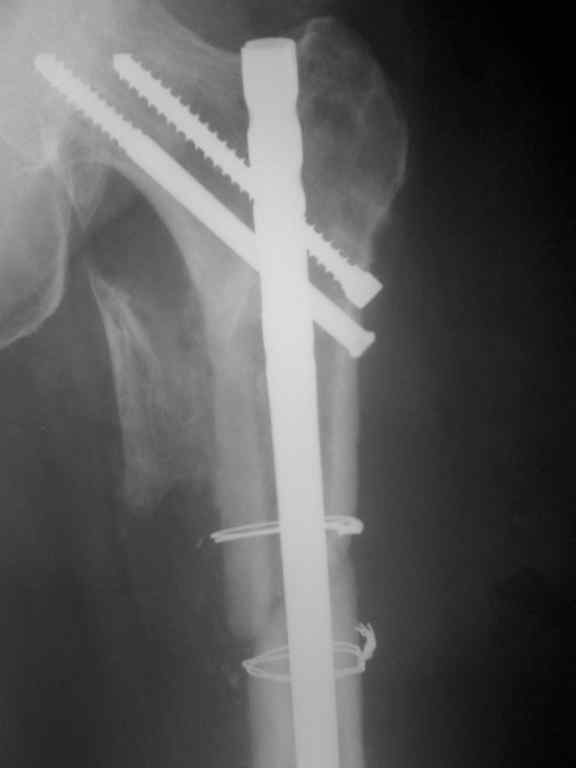

[Ortho] Несросшийся перелом бедра.Выбор операции?

Р-гр после реостеосинтеза